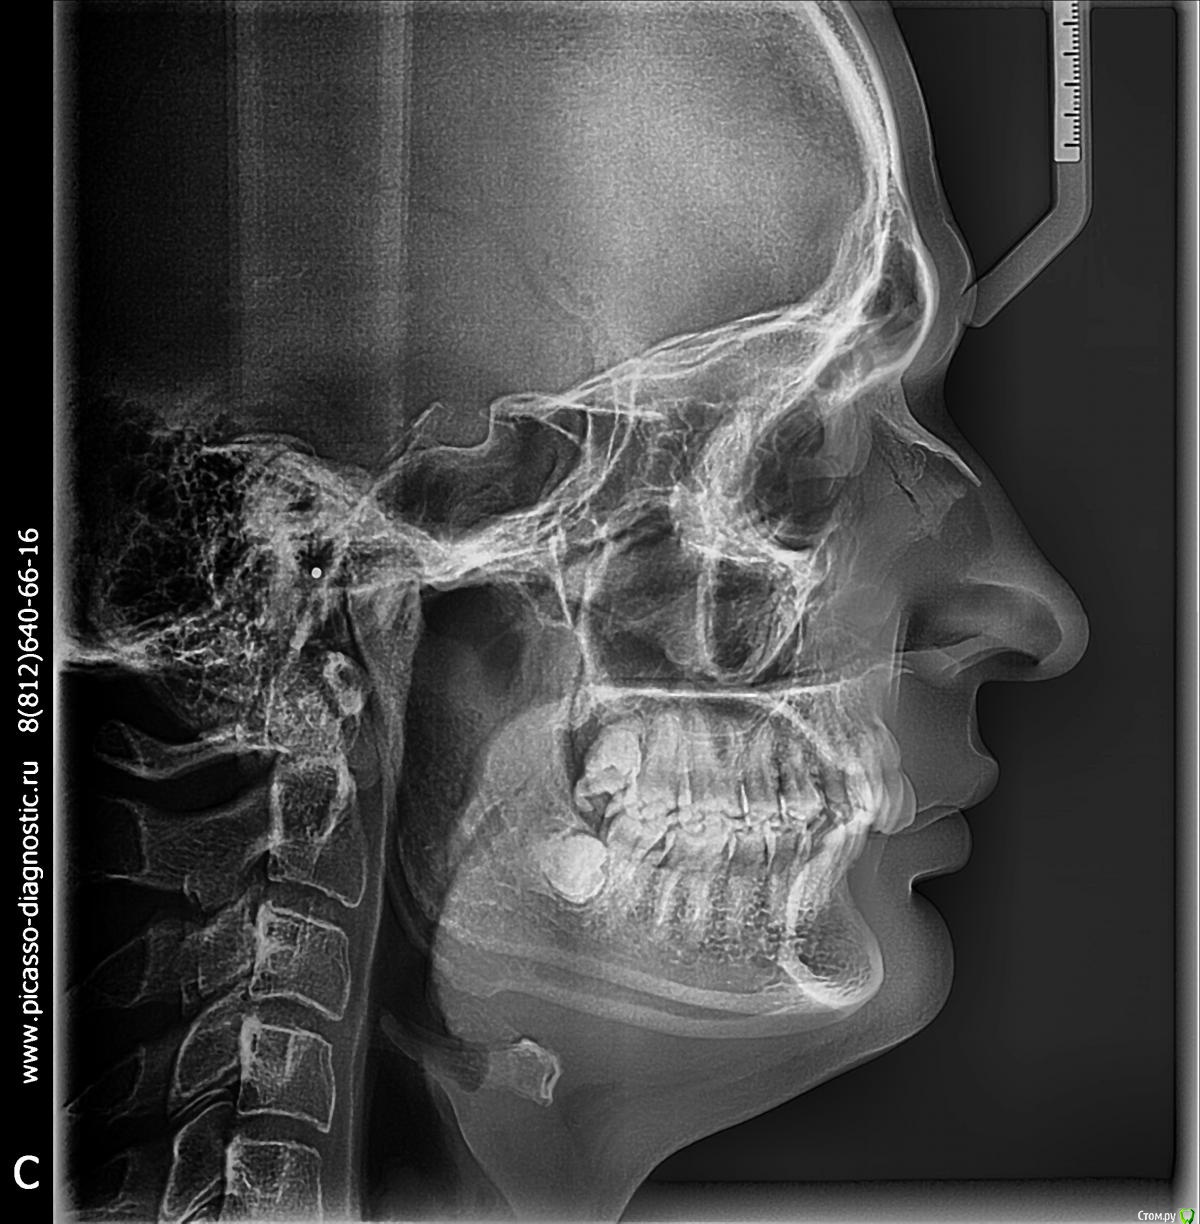

Мне 28 лет. У меня нет ни одной пломбы. Всю жизнь я хожу к стоматологом только на гигиеническую чистку. Последние несколько лет мне уже несколько врачей рекомендовали удалить четвёрки и поставить брекеты для исправления дистального прикуса. Один из ортодонтов также предлагал ЧЛХ нижней челюсти. Основной аргумент у врачей, что если не снизить нагрузку на дёсны от неправильного прикуса, то уже лет через 5 зубы начнут выпадать. Как видно на фото, дёсны уже значительно сползли, появился клиновидный дефект. С эстетической точки зрения меня всё устраивает. Хочу услышать ещё несколько мнений, как бороться с опусканием дёсен и стоит-ли заниматься исправлением прикуса.